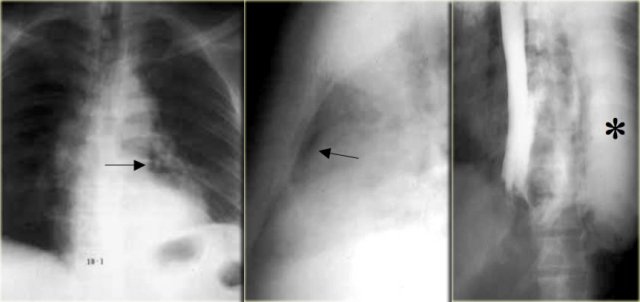

This image is of a patient with Boerhaave syndrome.

Chest radiographs show pneumomediastinum (arrows).

Esophagram with extravasated water soluble contrast material in left hemithorax (asterisk)

Perforation is almost always on the left side of distal esophagus.

Radiographs show mediastinal gas, effusion, and later pneumothorax.

Esophagram is used to confirm leak, first with water-soluble contrast, then barium if no leak is demonstrated.

On the left a patient with Boerhaave syndrome.

The barium study shows extraluminal gas (arrow) without contrast extravasation.

CT shows extraluminal gas (arrows).

Rent of distal left esophagus confirmed at surgery.

CT can show small amounts of extraluminal gas or extravasation not visible on radiographs or esophagram.